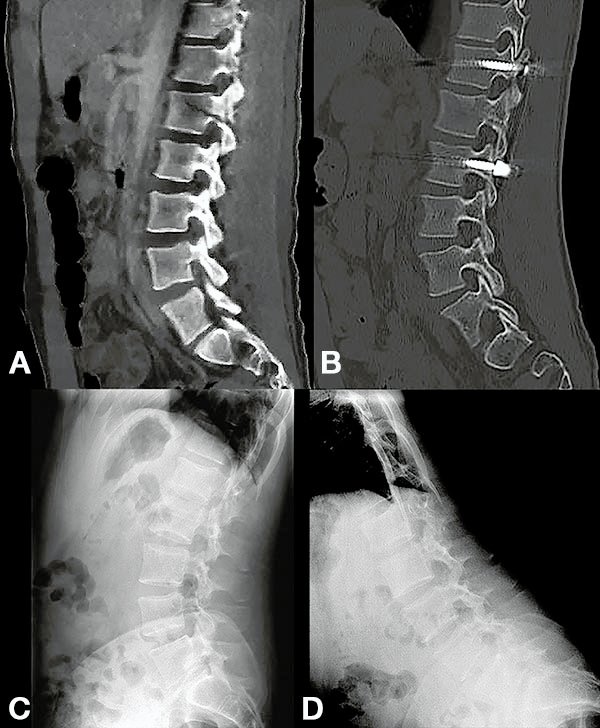

Figura 1:

Caso 24. Hombre 21 años con politraumatismo por accidente vial. A y B: Fractura del cóndilo occipital izquierdo. C: Fractura expuesta del húmero izquierdo y clavícula. D: Contusión pulmonar más hemotórax derecho.

Figura 2:

Caso 24. A y B: Fractura horizontal que compromete cuerpo, pedículo izquierdo y apófisis espinosa de L1 (L1: B1; N1 AOSpine). C y D: Estabilización percutánea T12-L2.

Figura 3:

Caso 24. A: Fractura L1: B1; N1. B: Control 7 meses que evidencia consolidación. C y D: Retiro de osteosíntesis a los 9 meses con buena movilidad en las radiografías dinámicas de control.